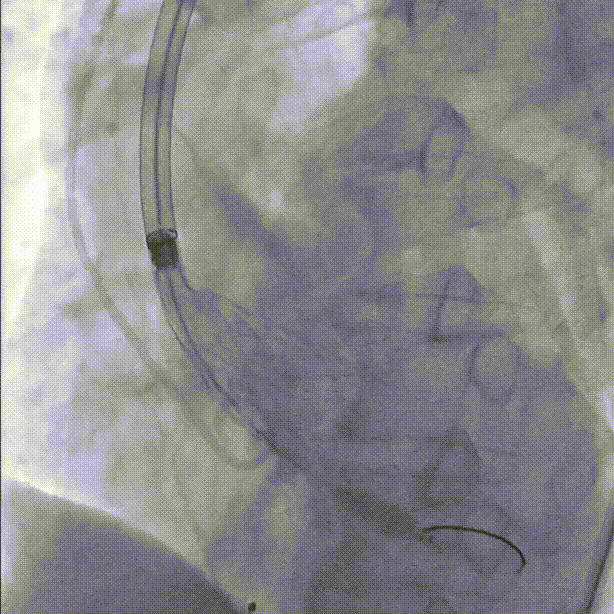

直头导丝跨瓣:

导管测压,压力阶差60mmHg:

球囊预扩张:

初始定位,左右窦重叠视图开始释放:

释放中期,快速起搏下释放到80%切换视图,并借助食管心超评估深度和反流情况:

完全释放和瓣膜脱钩: